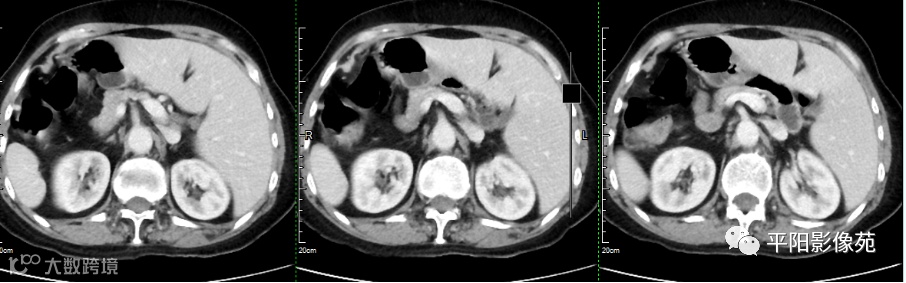

影像检查

全内脏翻转并左侧阑尾炎

完全内脏转位是指心脏、肺部、横膈及腹腔脏器等全部内脏呈180°转位,因此又被称为“镜面人”,其发生率0.5/10 000~2/10 000。